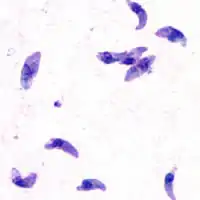

Morfología

Las distintas fases de desarrollo del Toxoplasma gondii muestran cambios importantes en su morfología, estas son llamadas: #Taquizoito, #Bradizoito y #Ooquiste.

El Taquizoito es la forma de la infestación aguda, tiene de 4-8 micrómetros (μm) (micrómetros) de longitud y de 2-4 μm de ancho, con aspecto de medialuna.

Un grupo de estructuras moleculares, en un extremo del Taquizoito del T. gondii, con la denominación de complejo apical, es fundamental tanto para la invasión como para la proliferación de este parásito.[4][5]

Taquizoito

Los taquizoitos son formas mótiles que forman pseudoquistes en tejidos infestados por toxoplasma. Los taquizoitos se encuentran en vacuolas dentro de las células, esta forma celular invade y se replica en las células infectadas. Activan el sistema inmune y se convierten en bradizoitos que se dividen lentamente.